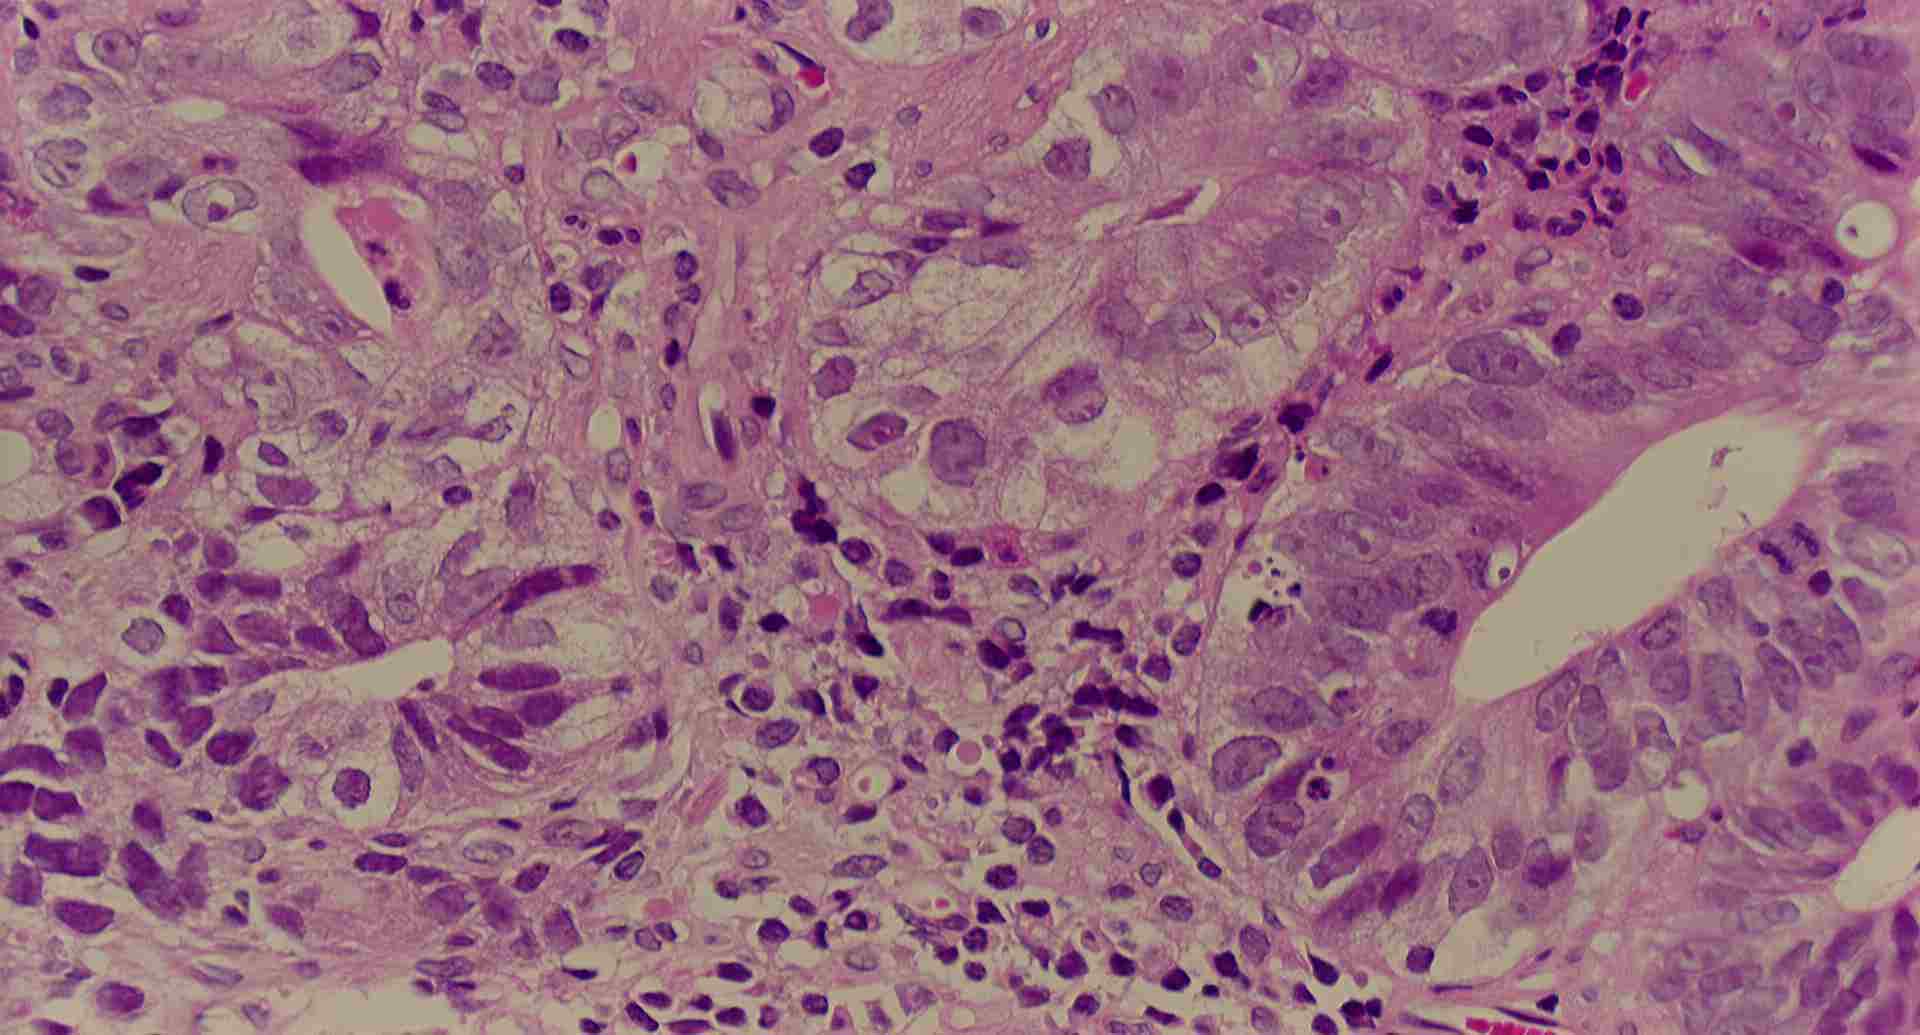

標本9

標本9の説明